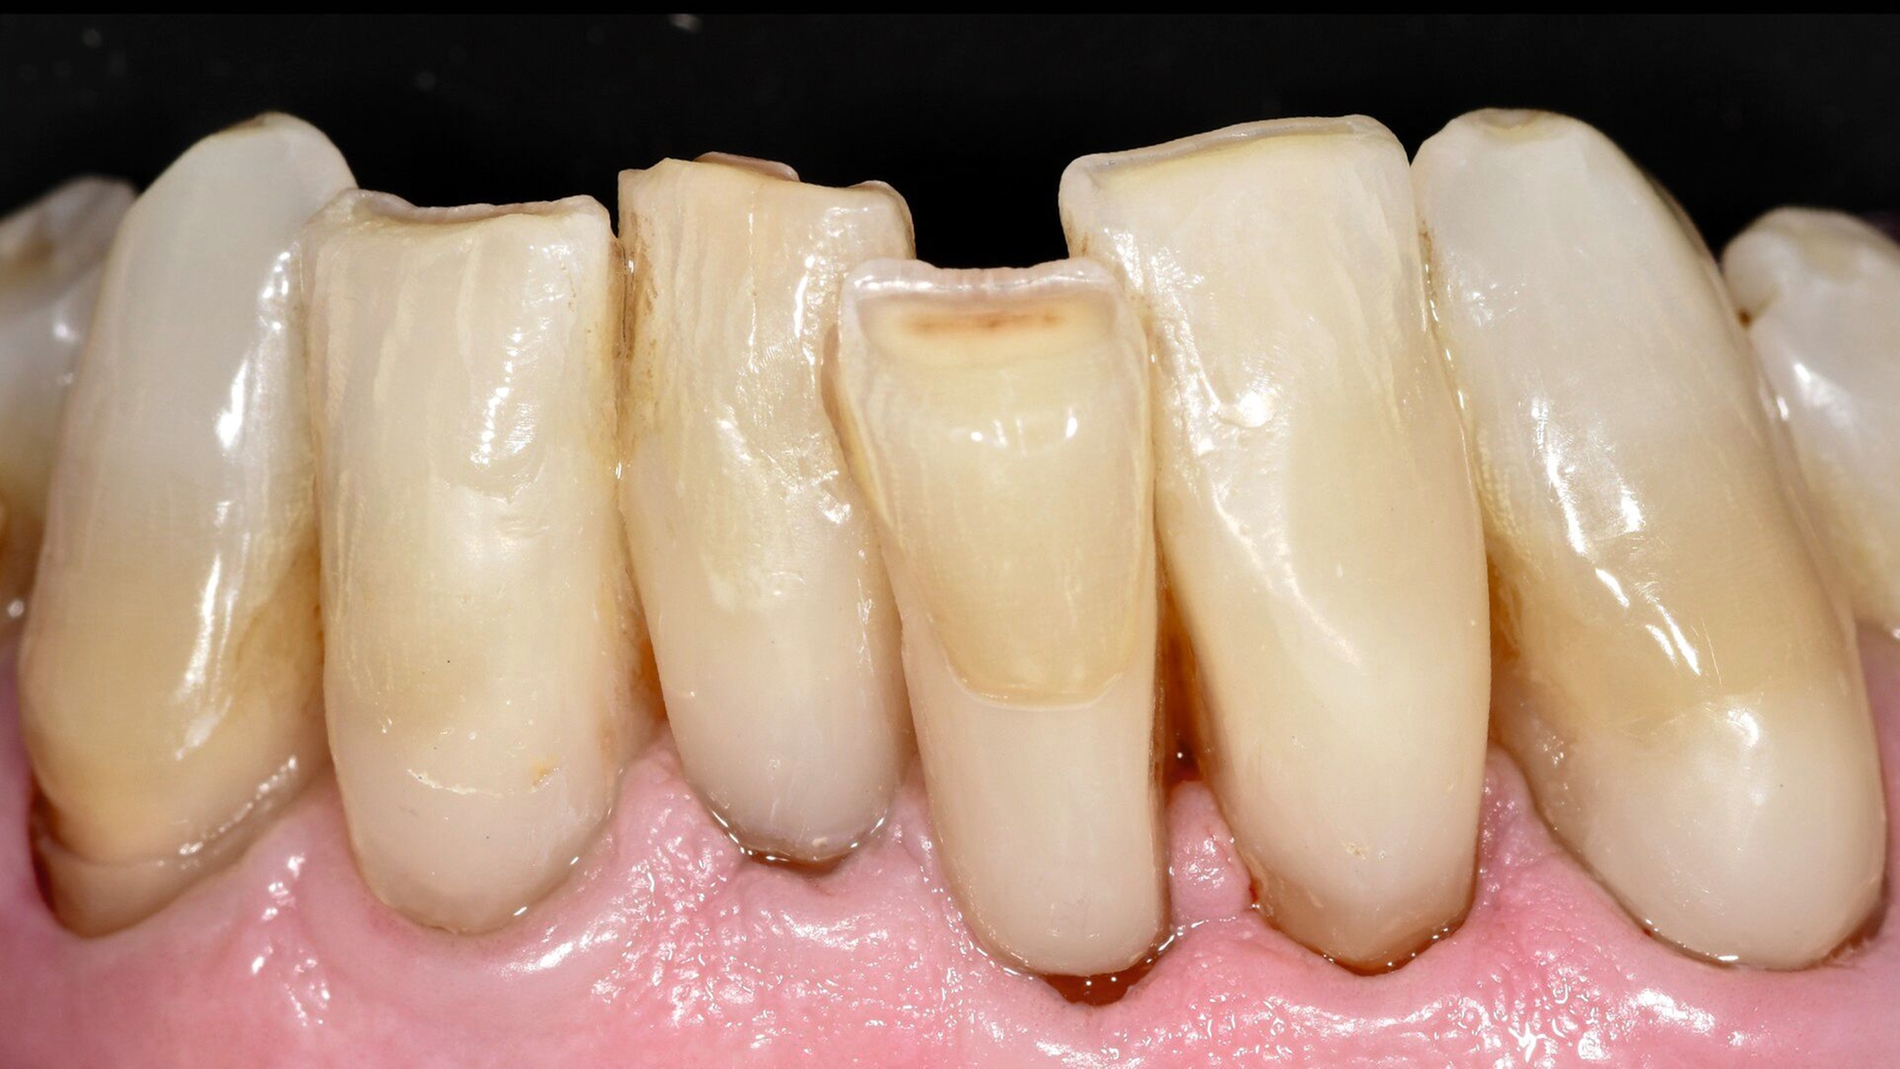

Ein sich seit vielen Jahren bei mir in Behandlung befindlicher 75-jähriger Patient klagte zunehmend über Hypersensibilitäten an den unteren Frontzähnen, die im Zahnhalsbereich ausgeprägte Zahnhartsubstanzdefekte aufwiesen (Abbildungen 1a–1d). Die Mundhygiene wurde als gut eingestuft. Möglicherweise waren die vorliegenden Zahnhalsdefekte als sogenannte Putzdefekte zu klassifizieren, wie sie bei intensiven Mundhygienebemühungen häufig zu beobachten sind.

Mit zunehmendem Alter hatte der Patient allerdings Mühe, die schwer zugänglichen Defekte adäquat zu reinigen. Zudem musste man befürchten, dass es bei weiterem Abbau der Zahnhartsubstanz in diesen Bereichen zu einem Verlust der Zahnintegrität oder einer Pulpaexposition kommt. Daher wurde entschieden, die besonders stark betroffenen Zähne 31, 32, 41 und 42 mit Kompositrestaurationen im Zahnhalsbereich zu versorgen.

Zwei Jahre nach Restauration der unteren Inzisivi wurde deutlich, dass der Patient auch an Zahn 33 den vorliegenden Zahnhalsdefekt nicht mehr ausreichend reinigen konnte. Daher wurde entschieden, auch diesen Zahn mit einer Kompositrestauration zu versorgen (Abbildung 1d).